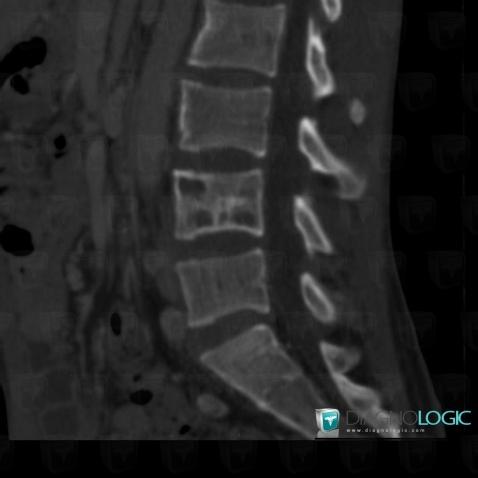

Tuberculosis, Vertebral body / Disk, Theoretical

Here is the specific information in the key image above:

- Diagnosis Tuberculosis (link to Osteomyelitis), Location(s) Vertebral body / Disk, with gamuts Discal / Intraverbetral gaz